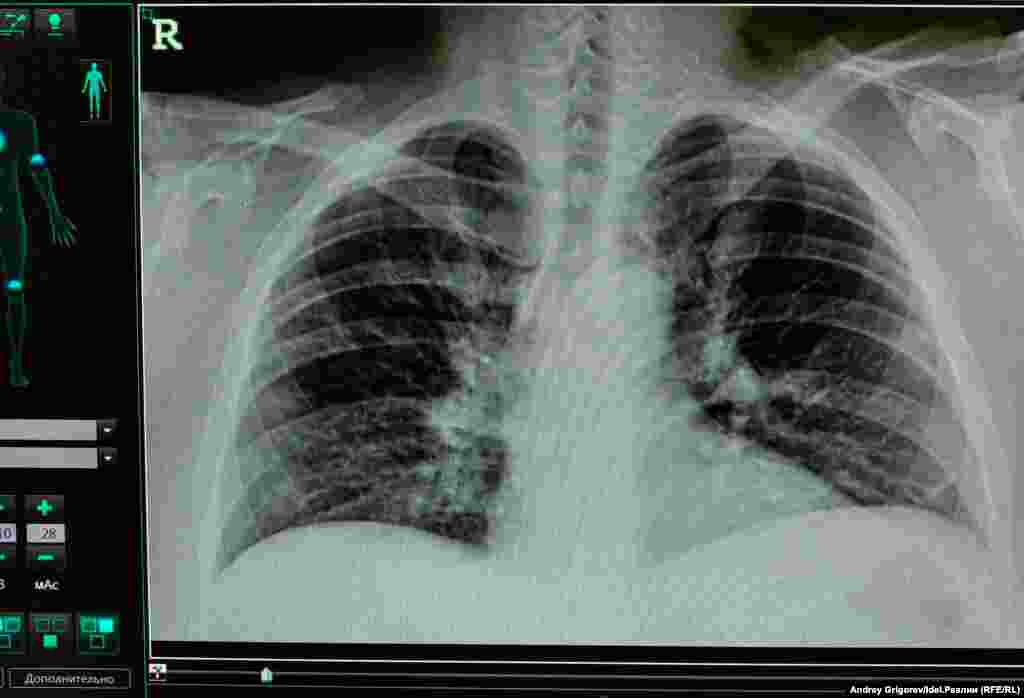

Временный ковидный госпиталь при РКБ

Временный ковидный госпиталь при РКБ является резервным и занимает здание отделения травматологии. Корреспондент Idel.Реалии находился в нем с 4 по 17 июля.